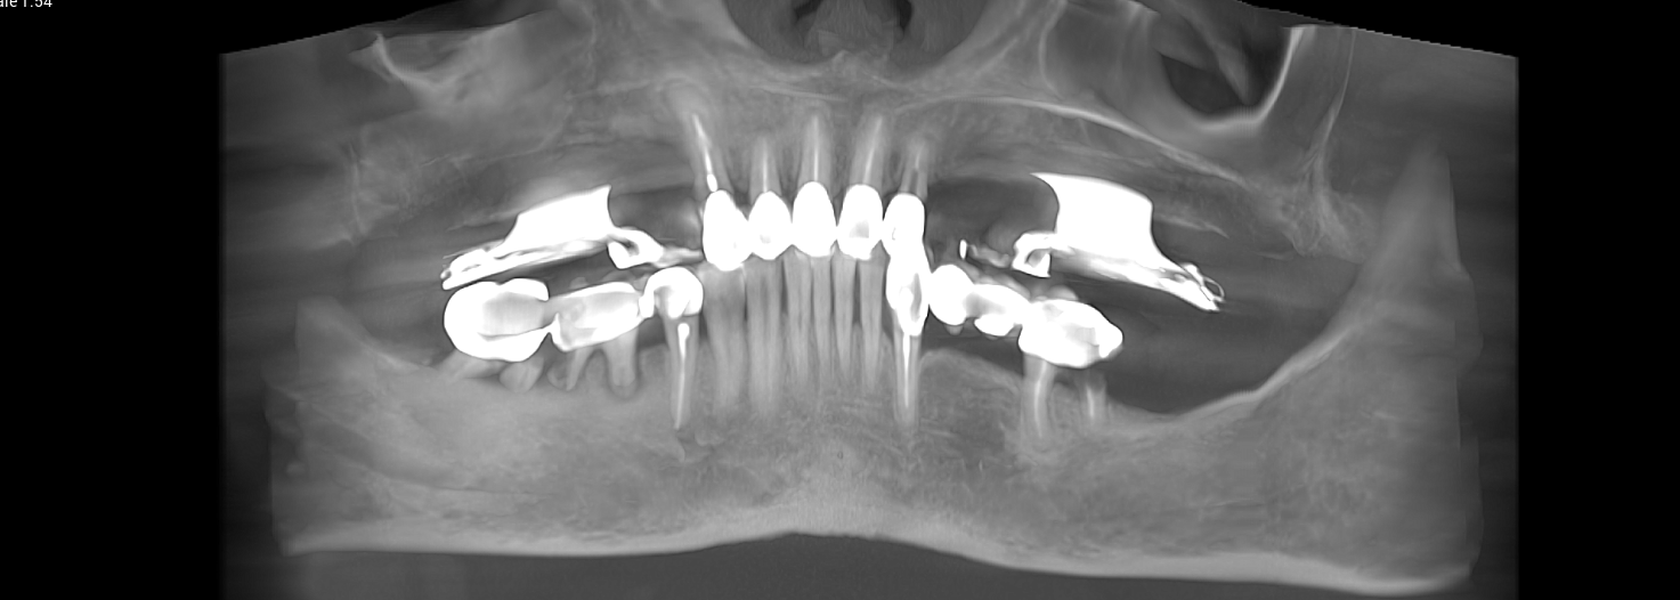

Tomografii (CBCT)

- Investigație imagistică completă, ideal CBCT (computer tomografie);